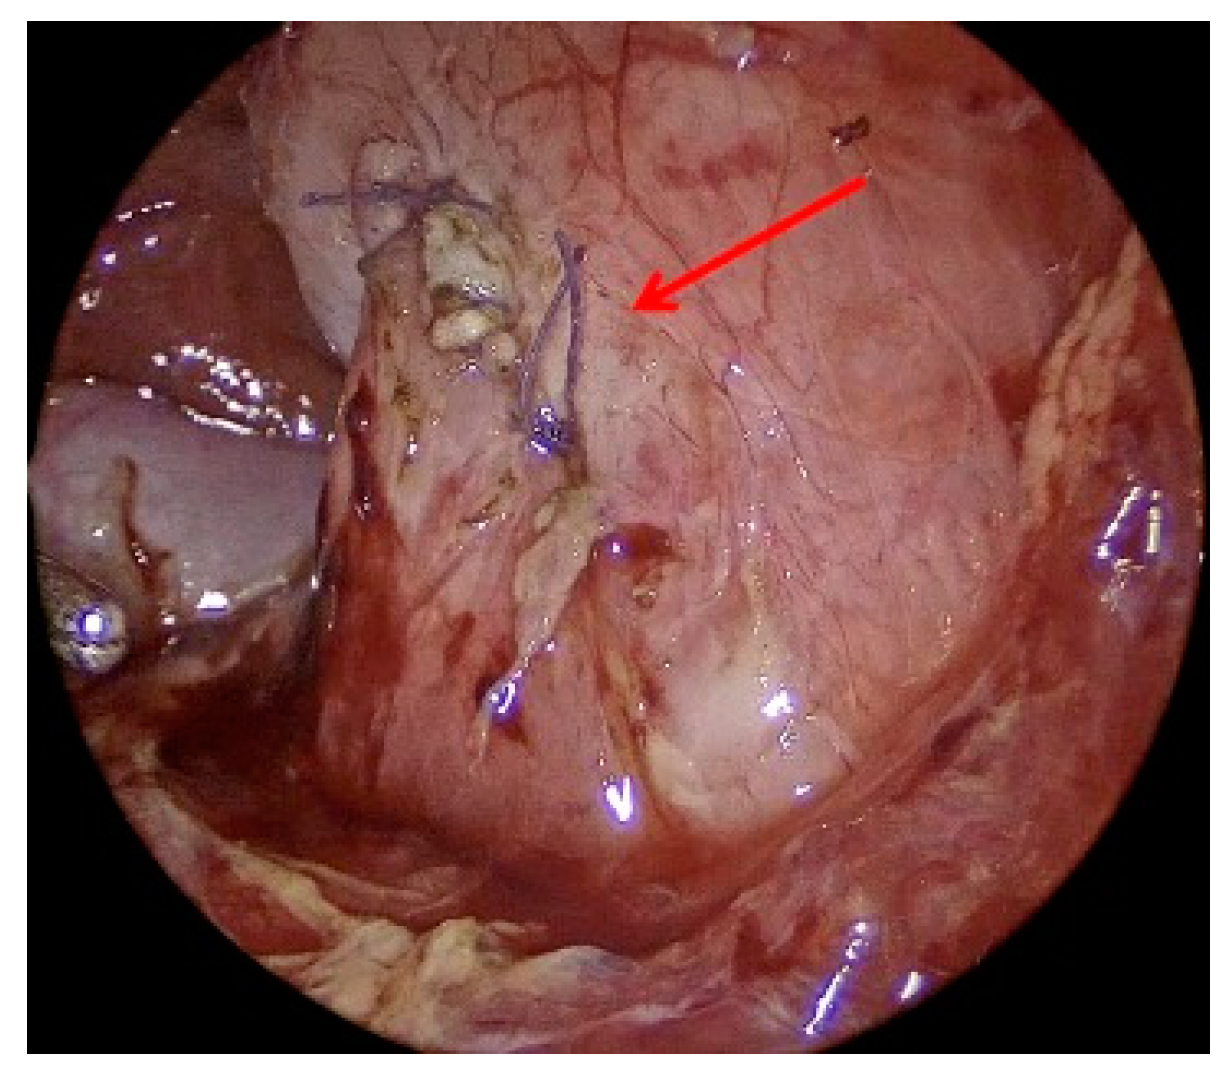

2.4.2. Laparoscopic Resection

2.4.3. Duodenal Web Localization